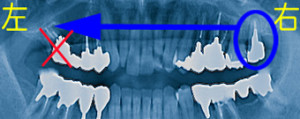

移植で自前のインプラント

コラム「移植で自前のインプラント」の画像